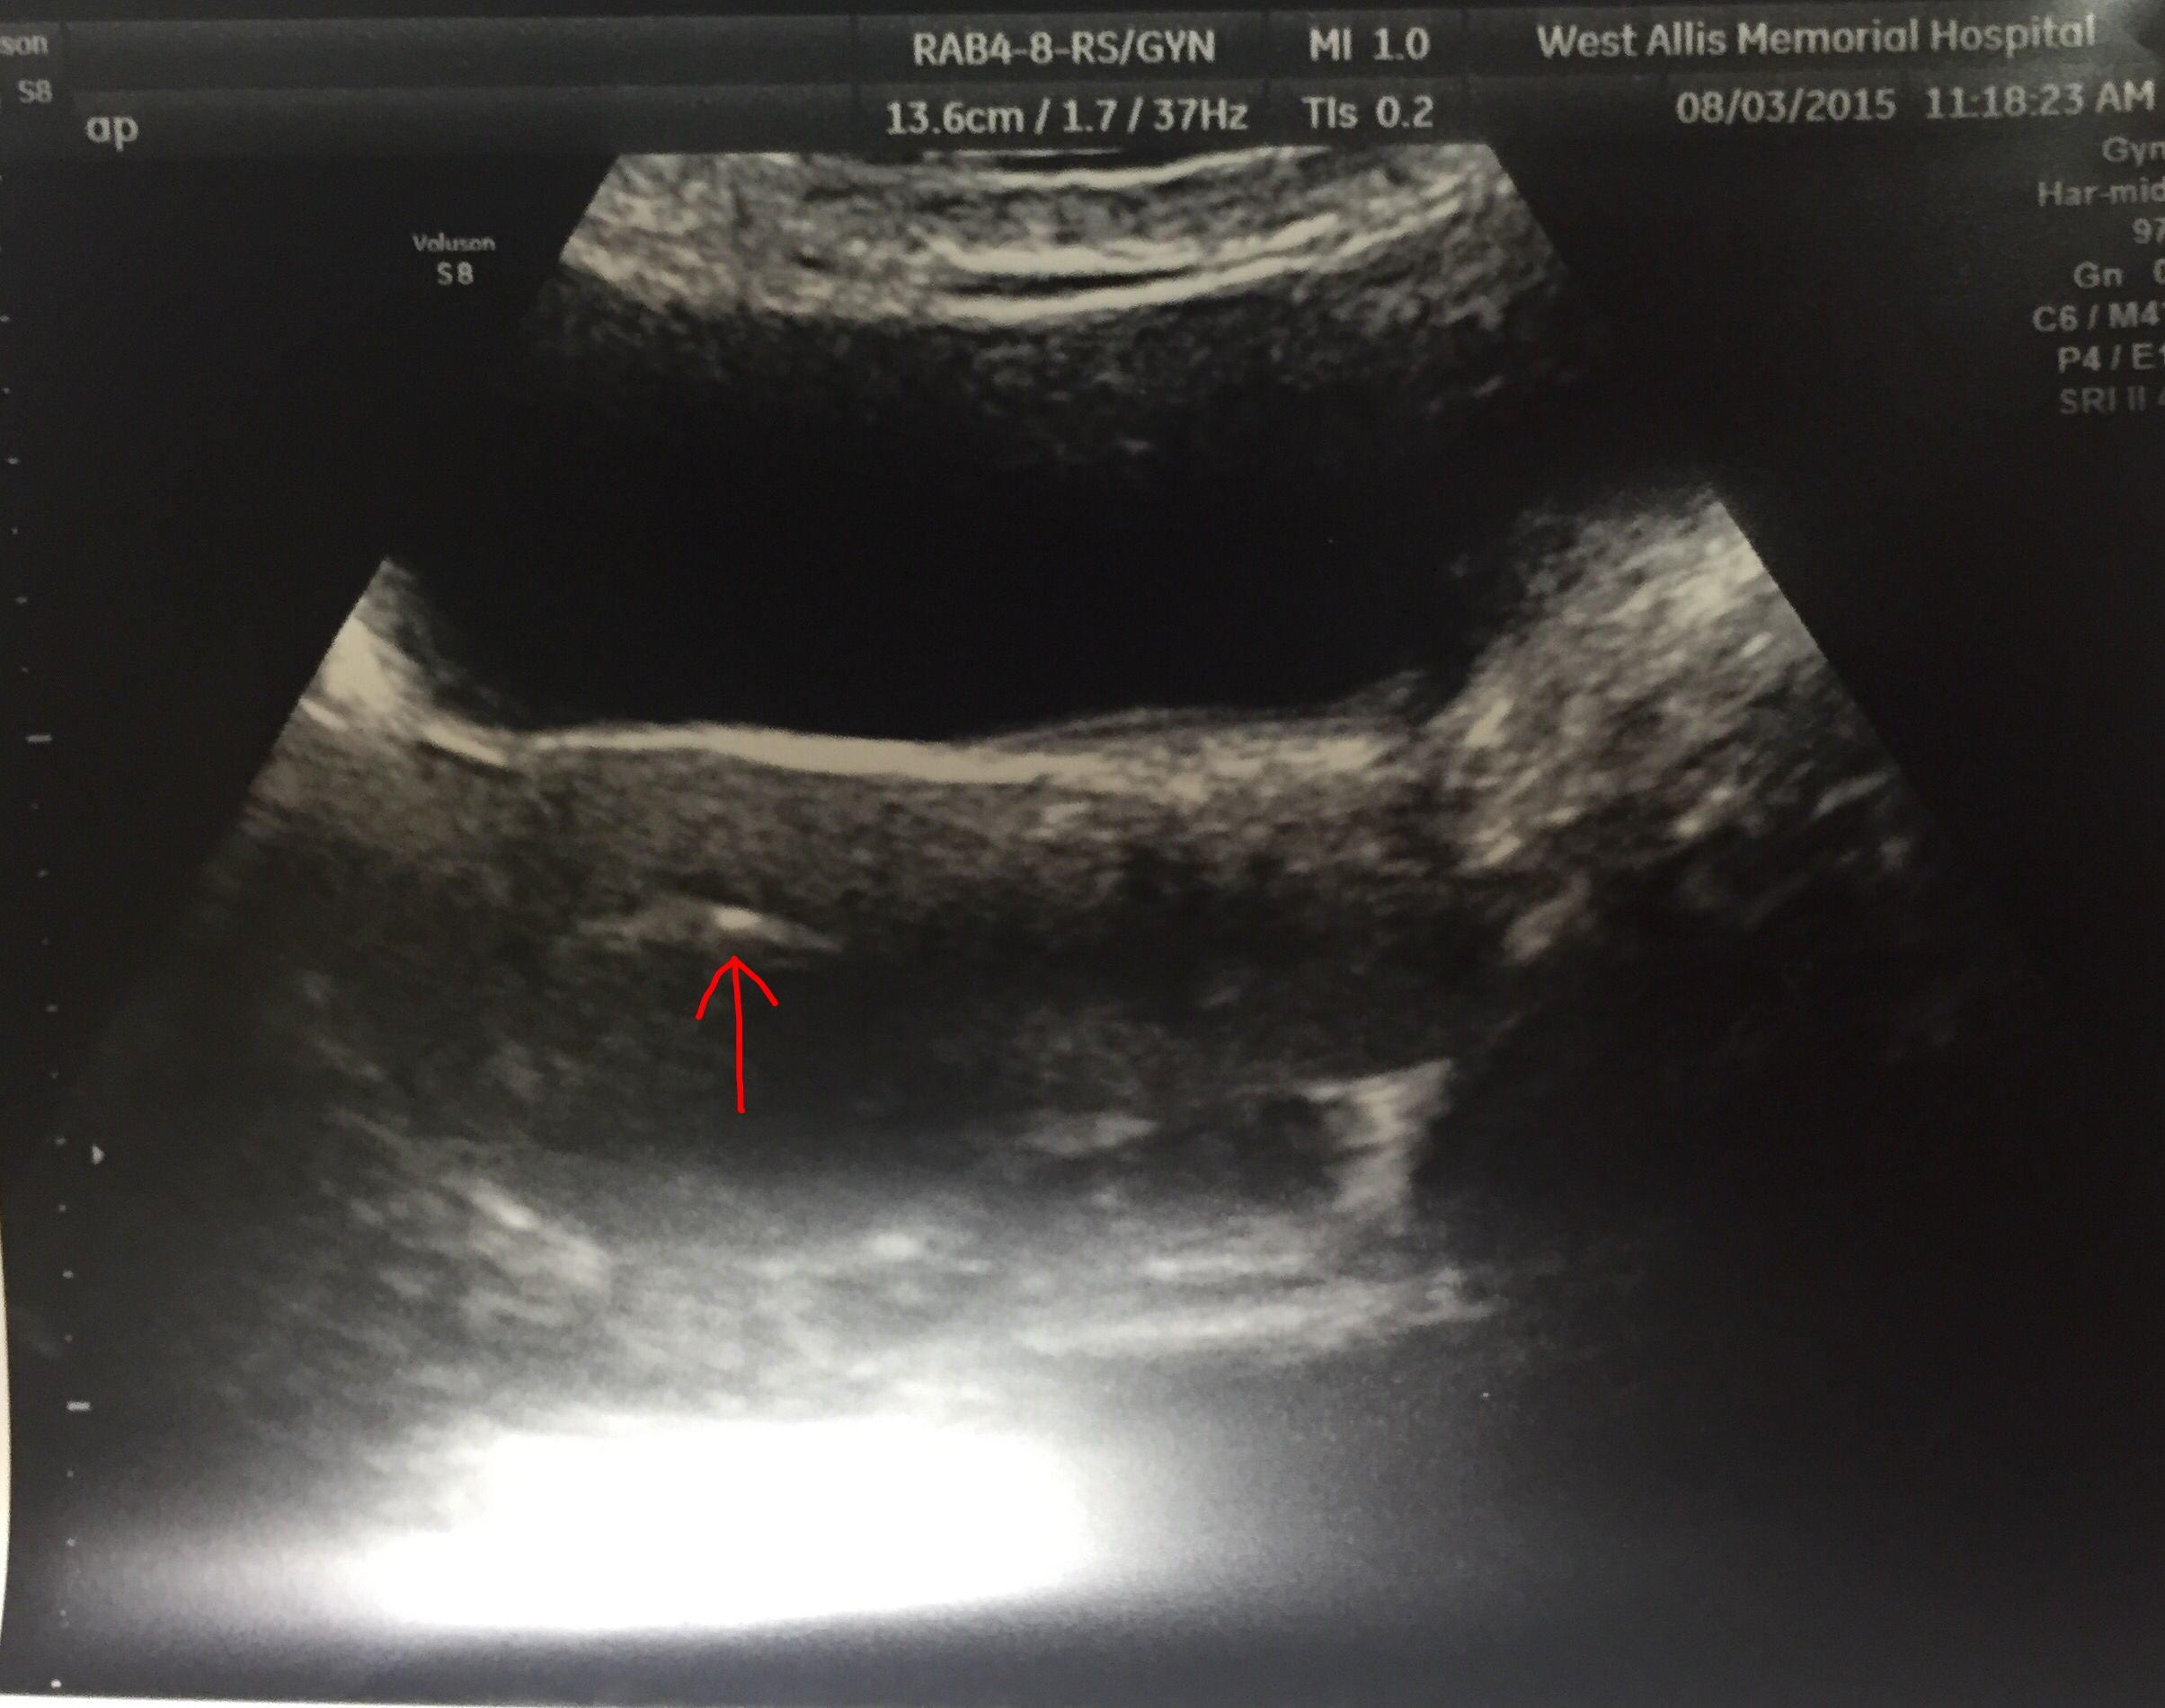

Ricky and I had our 6 1/2 week ultrasound this morning and we learned we are expecting twins! Both babies had a heartbeat that we could see on the ultrasound and measured well.

We have our next ultrasound in 2 weeks.